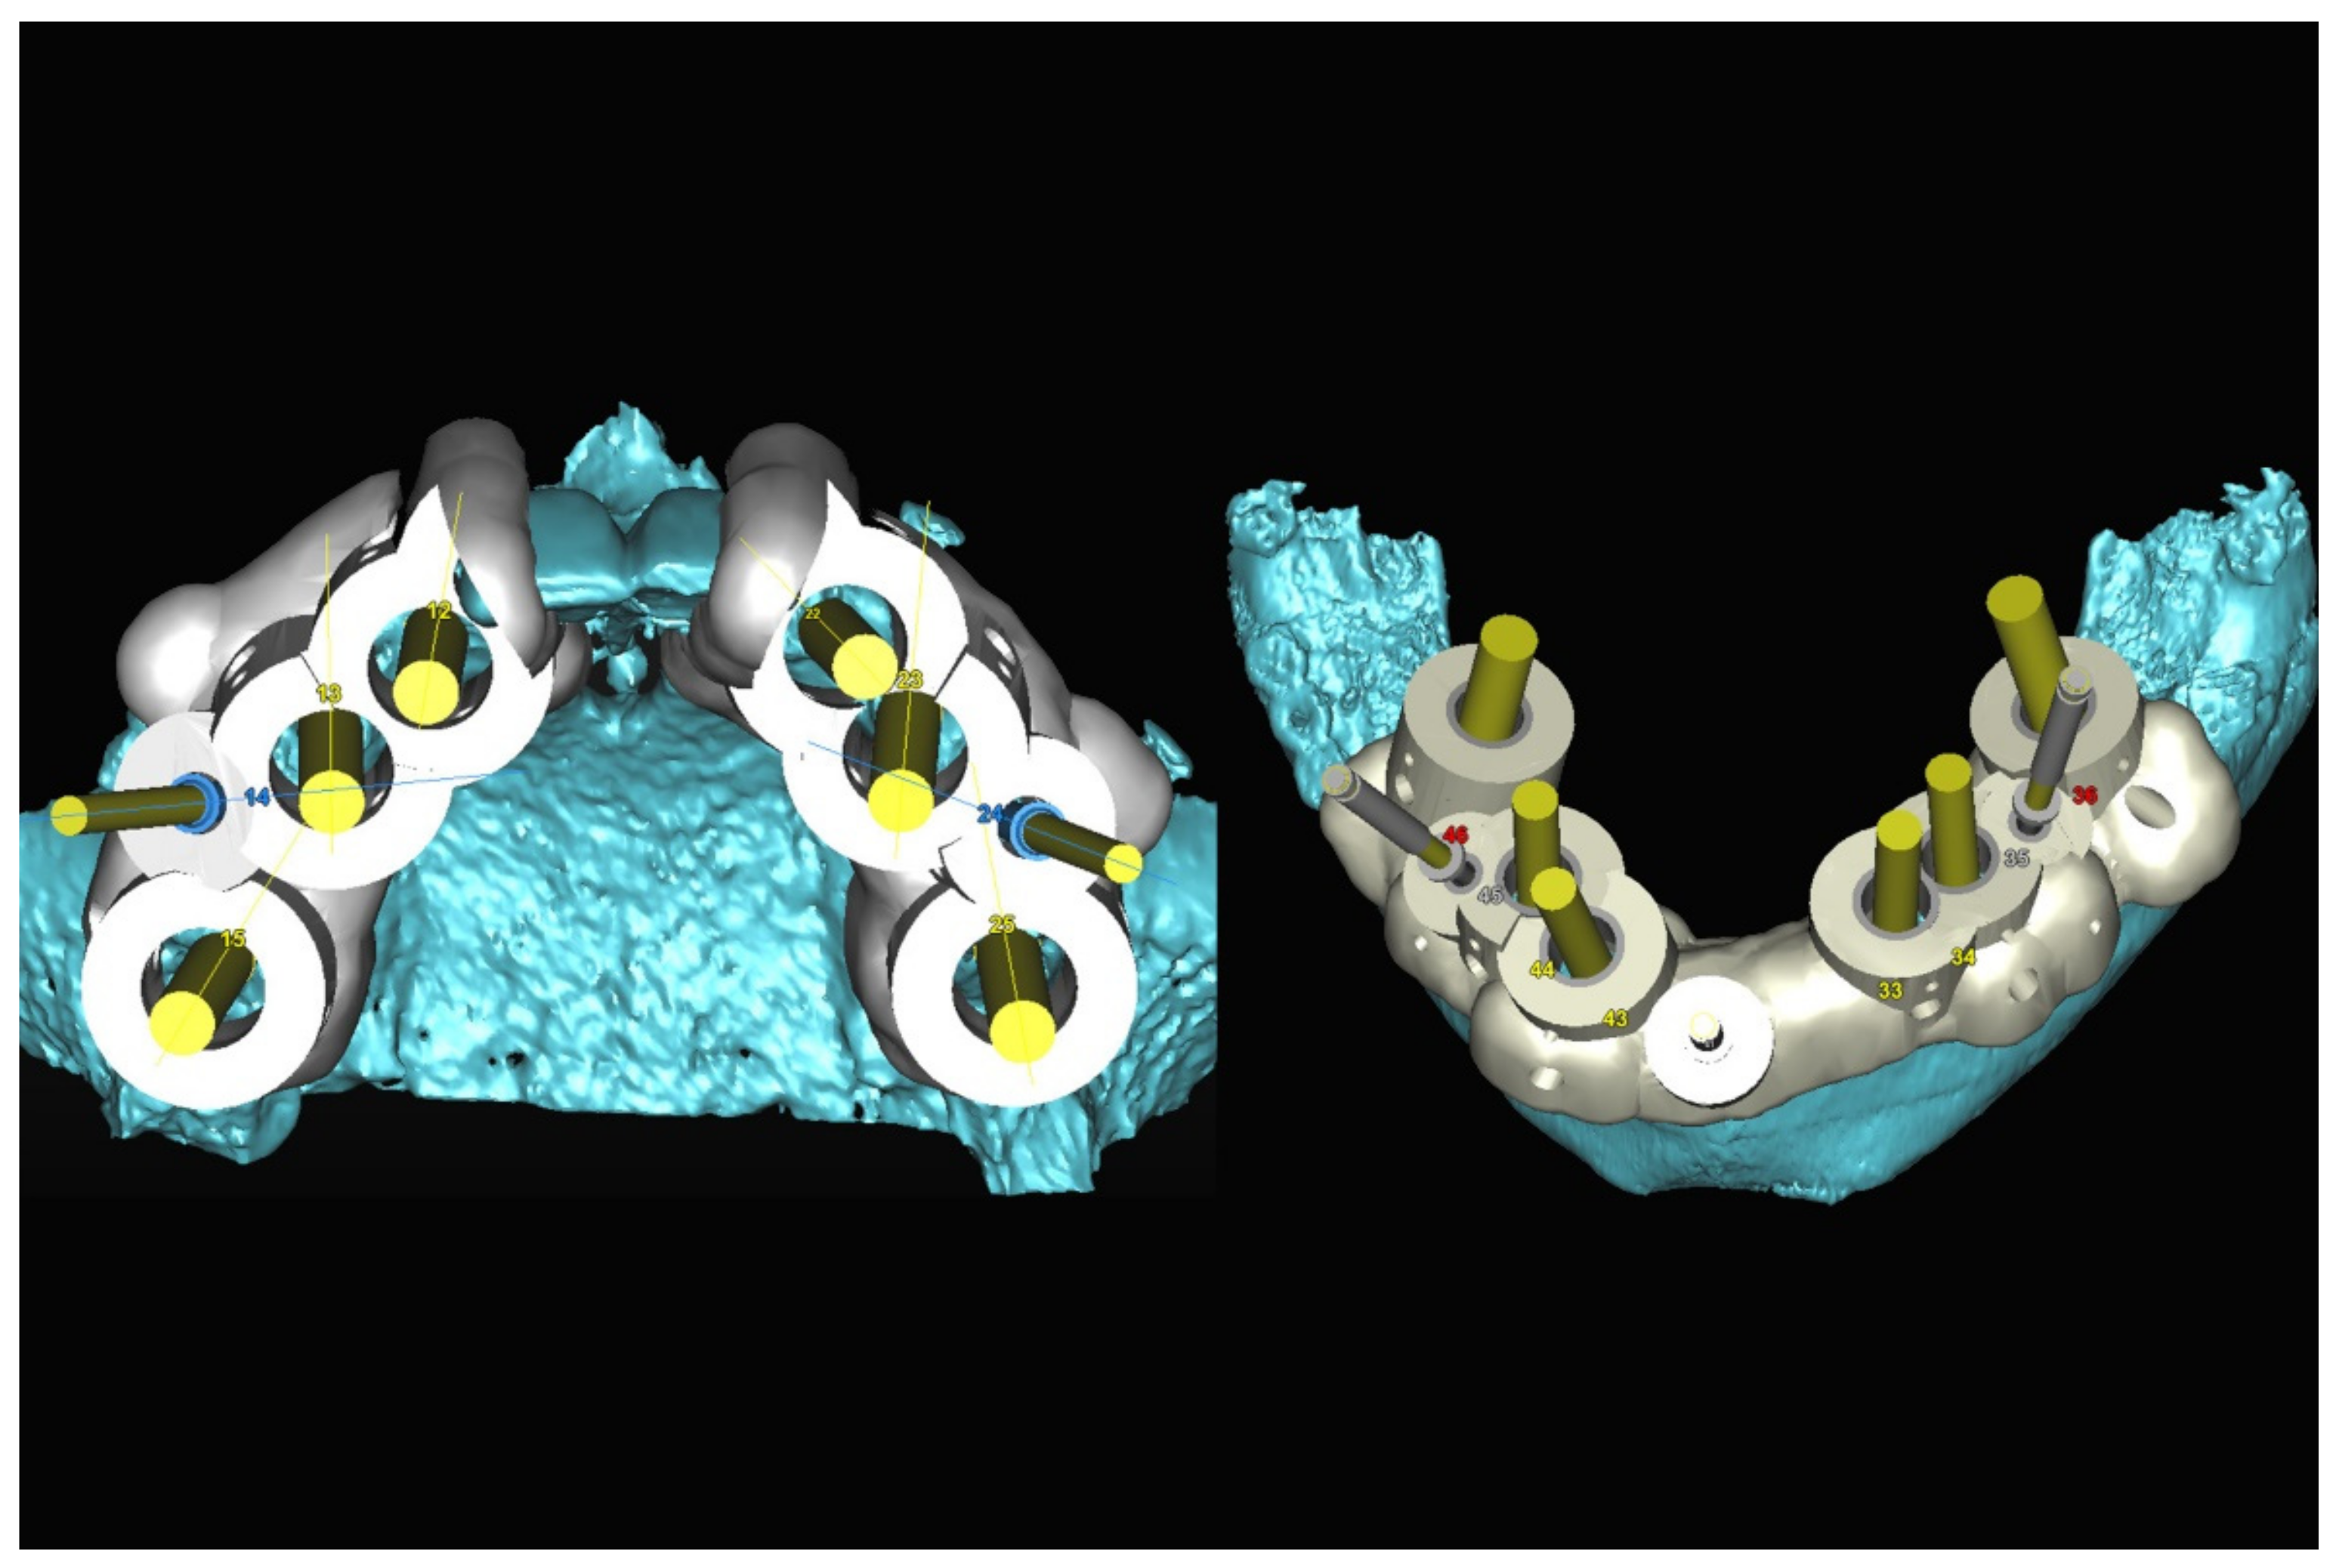

3.4. Step 4: Manufacturing of the Surgical Stereolithographic Drilling Guide

6.3.3. Image Segmentation and Virtual Planning:

6.2.3. Image Segmentation and Virtual Planning: